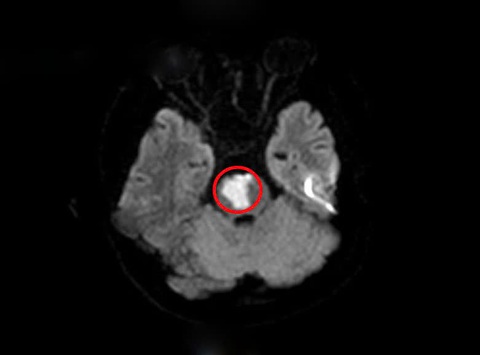

Tổn thương nhồi máu vùng tiểu não của người bệnh (vùng khoanh tròn màu đỏ) - Ảnh: BVCC

Sau khi khai thác tiền sử, các bác sĩ nghĩ nhiều đến tình trạng đột quỵ não và cho chỉ định tiến hành chụp MRI sọ não. Kết quả cho thấy người bệnh có khối nhồi máu tiểu não, cầu não do tắc động mạch thân nền.